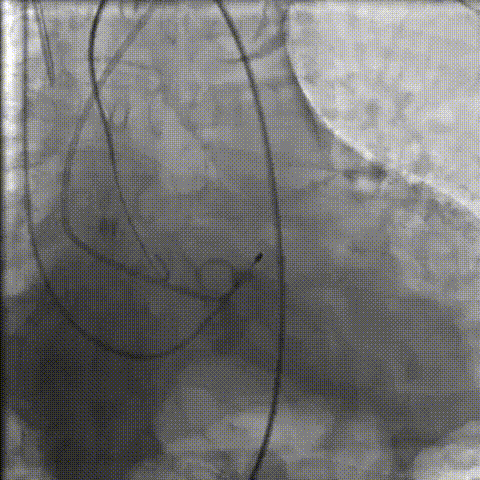

术中剪影